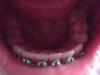

На данный момент находимся на отметке:

Вч - 7 месяцев 2 дня

Нч - 5 месяцев 1 день

Кажись, поехал центр) Ну да ладно, со всем разберемся. Нч все не желает исправляться

Как обычно немного пропускаю даты, потому что охото прием описать. Вернулась только что из больницы, слава Немо (да да, я прославляю кота) врач была там. Села в кресло, ортоша достает страшный прибор с иголкой. Мысленно паникую... Начала сверлить. Поскольку мне начали наш вечный разговор о налете, постепенно поняла что там происходит. Закончив свое дело, отрофеюшка надела мне чейн! Никогда не думала, что он у меня будет

Ну да ладно, вытирая кровь, подумала я. Отважилась было уже спросить про тяги как... правильно, орта сама о них упомянула. Посидела на стульчике, дождалась медсестры и поставили мне моих "жарких" помощников

Носить весь день с шестерки Вч на клык Нч (вдруг забуду), менять раз в день. Рада была конечно безумно. Теперь пыл спал... Поела сейчас, давай одевать. А как? Как как - крючком!

Ну, вроде бы все. Ловите как обычно фото